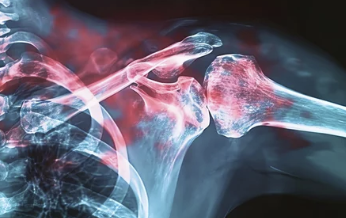

쇄골 골절 치료 방법은 골절의 위치, 파편 상태, 환자의 나이에 따라 다르게 결정돼요. 비수술적 치료와 수술적 치료 두 가지 방법이 있어요.

- 비수술적 치료: 비교적 간단한 골절의 경우, 팔걸이(슬링)나 브레이스를 이용해 뼈가 자연스럽게 붙을 수 있도록 고정해요. 비수술적 치료는 일반적으로 회복 기간이 길지만, 합병증 발생 위험이 적어요.

- 수술적 치료: 뼈가 여러 조각으로 부서졌거나 골절 상태가 복잡한 경우에는 금속판이나 나사로 뼈를 고정하는 수술적 치료가 필요해요. 수술적 치료는 빠른 회복을 기대할 수 있지만, 수술 후 합병증 가능성에 주의해야 해요.